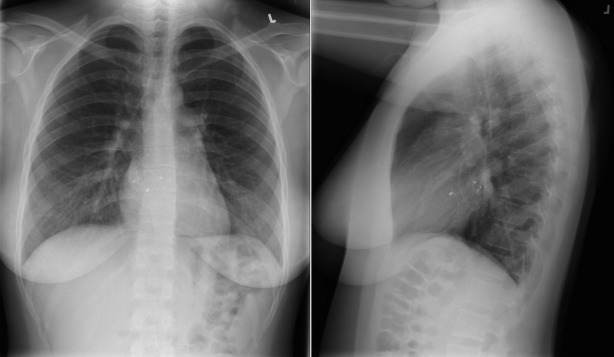

A patent foramen ovale is present in 25% to 30% of the adult population ( Figs. 18-1 to 18-4 ). Any magnitude of shunting across it in normal circumstances is undetectable radiographically. Percutaneous patent foramen ovale closure devices are fairly commonly inserted and are radiographically evident.